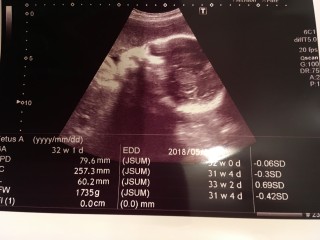

写真:32w1d:ケイトさん:こんなに開いたパー

なかなかお顔を見せてくれない息子ちゃん、今日のエコーでは手のひらを大きく開いてパーをして顔を隠していました(笑)先生もこんなに開いたパーをは珍しいね、と言ってくれました(^^)